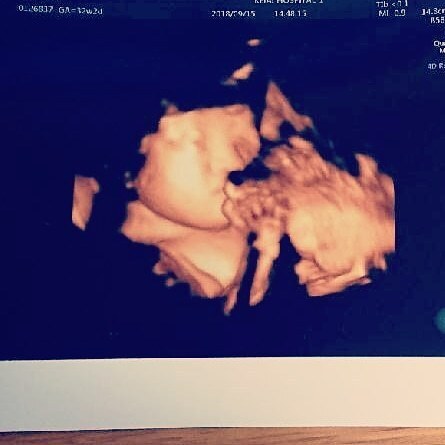

32週5日(32w5d・男の子)|おしげ さん(23歳)

エコー写真撮影時のエピソード:

妊娠9ヶ月の頃の写真です。福岡にいた私が出産のため大分に着て初めての診察で、4Dエコーするのも初めてでした。 立体的にうつる我が子をみてニヤニヤが止まりませんでした。

旦那もリアルなお腹の中の映像に感動!我が子はほっぺに手をあて、口をムニュムニュしてました。かわいいかったです。元気に生まれてきてくれた今は幸せいっぱいです。